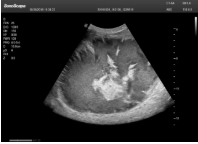

1單晶體凸陣探頭

采用了單晶體探頭材料,探頭面是凸面,接觸面小,成像視野呈扇形,應(yīng)用廣泛,常應(yīng)用于腹部、婦產(chǎn)、肺部等相對部位較深的臟器。

超聲圖像是探頭和系統(tǒng)平臺緊密結(jié)合的產(chǎn)物,因此在同一臺機器上,軟件、硬件都需要達到單晶探頭的要求。

肝癌